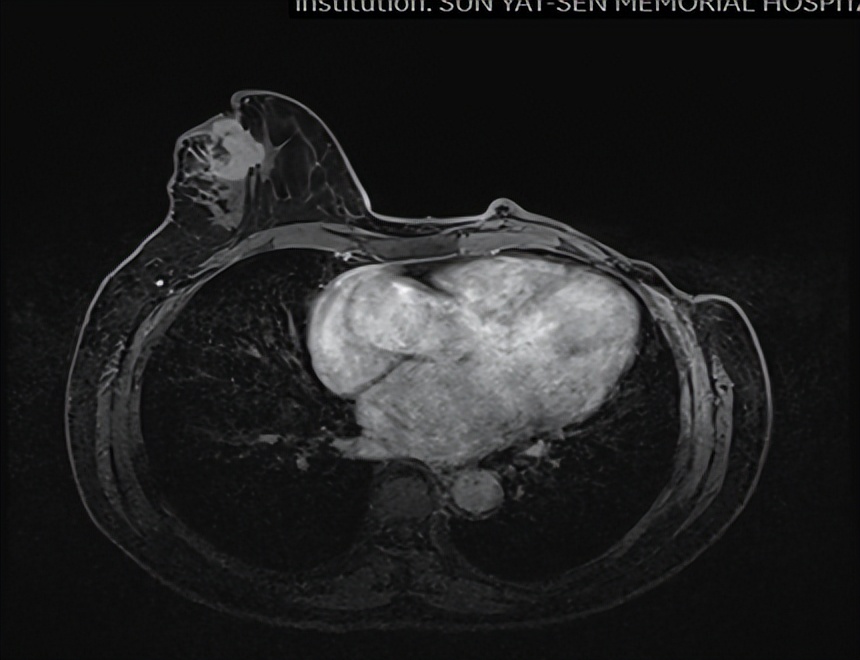

乳腺MR

右侧乳头后侧中部多个异常信号结节(较大者23*15mm),符合乳腺癌,BIRADS:5类。右侧腋下肿大淋巴结,考虑转移。

头颅+鼻咽部+颈部MR:右侧锁骨上区、所见上纵隔多发肿大淋巴结,考虑转移瘤。脑、鼻咽部未见明显异常。